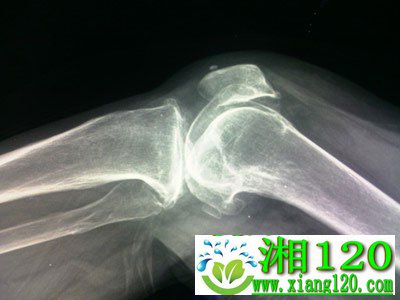

二、膝关节骨刺。患者一侧或双侧的膝关节都会产生不适感,或者会出现疼痛及肿胀。最初的疼痛表现出现在腿部长时间的活动后,休息后会有所好转。随着病情的加重,患者在走路时也会出现疼痛的感觉。由于关节不稳定,造成患者的活动不便,在活动时膝关节处还会发出捻头发一样的声音。更严重的情况是膝关节会突然被锁住,当恢复原位时会有明显的响声。